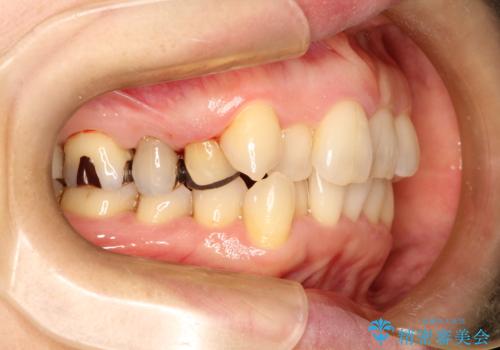

- 右上の八重歯(犬歯の突出)と、それに伴う歯並びのがたつきを主訴にご来院されました。精密検査の結果、八重歯を正しい位置に収めるためのスペースが大幅に不足していることが分かりました。

通常、矯正治療では4番目の歯を抜歯することが多いですが、今回は歯の状態や全体の噛み合わせのバランスを考慮し、右上5番(第二小臼歯)を抜歯してスペースを確保する計画を立案。装置には、周囲に気づかれずに治療を進めたいというご希望に合わせて、透明なマウスピース型のインビザラインを採用しました。

今回の治療では、右上5番の抜歯スペースを活用して八重歯(3番)を後方へ誘導しました。